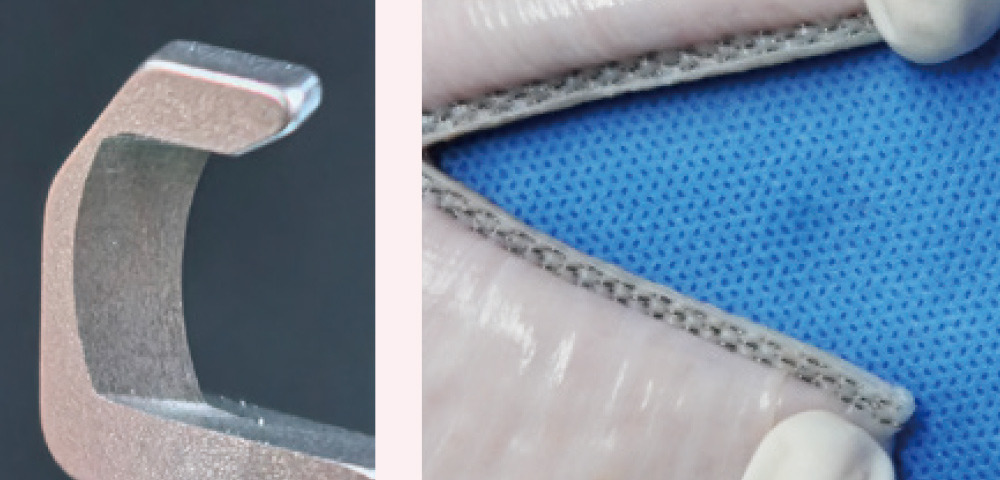

Reload designwith anti-slip & composite fiber

Increases friction between tissue and the jaws and effectively reduces tissue slippage. This stronger material reduces reload deformation when stapling on thick tissue, ensuring more secure staple formation.

Disposable knife blade

Reusable knife blade

Reusable knife blades tend to wear out after multiple use, causing jagged edges that increase the risk of bleeding.

Disposable knife blade from Mindray

A new knife blade for every single firing and tissue dissection,ensuring the smoother cutting edge for improved healing; single-use blade design also adheres to aseptic technique principles.